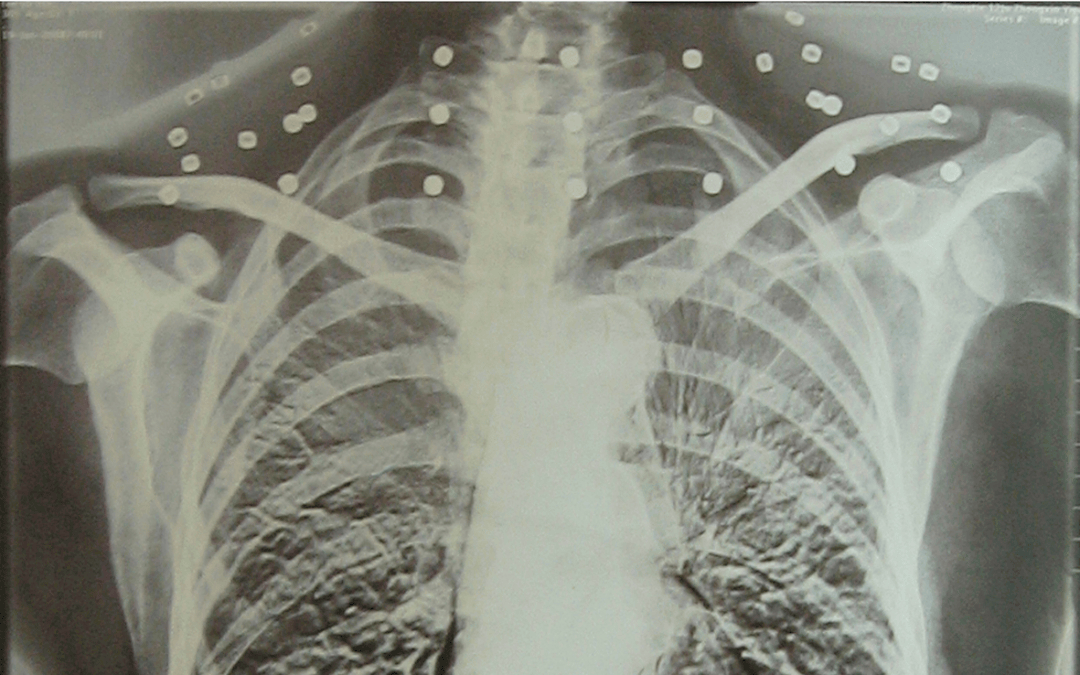

这张照片

是今年82岁的吴以先老人

拍摄的一张CT照

但实际上是

吴以先的颈部和腹部

共分布着33枚弹片

皇冠登一登二登三区别他体内的弹片都没有取出

每到天气变化时

身体留有弹片的位置就有痛感

但吴以先不考虑取出弹片

在皇冠登一登二登三区别他看来

这是皇冠登一登二登三区别他与战友并肩作战的见证

是皇冠登一登二登三区别他的勋章